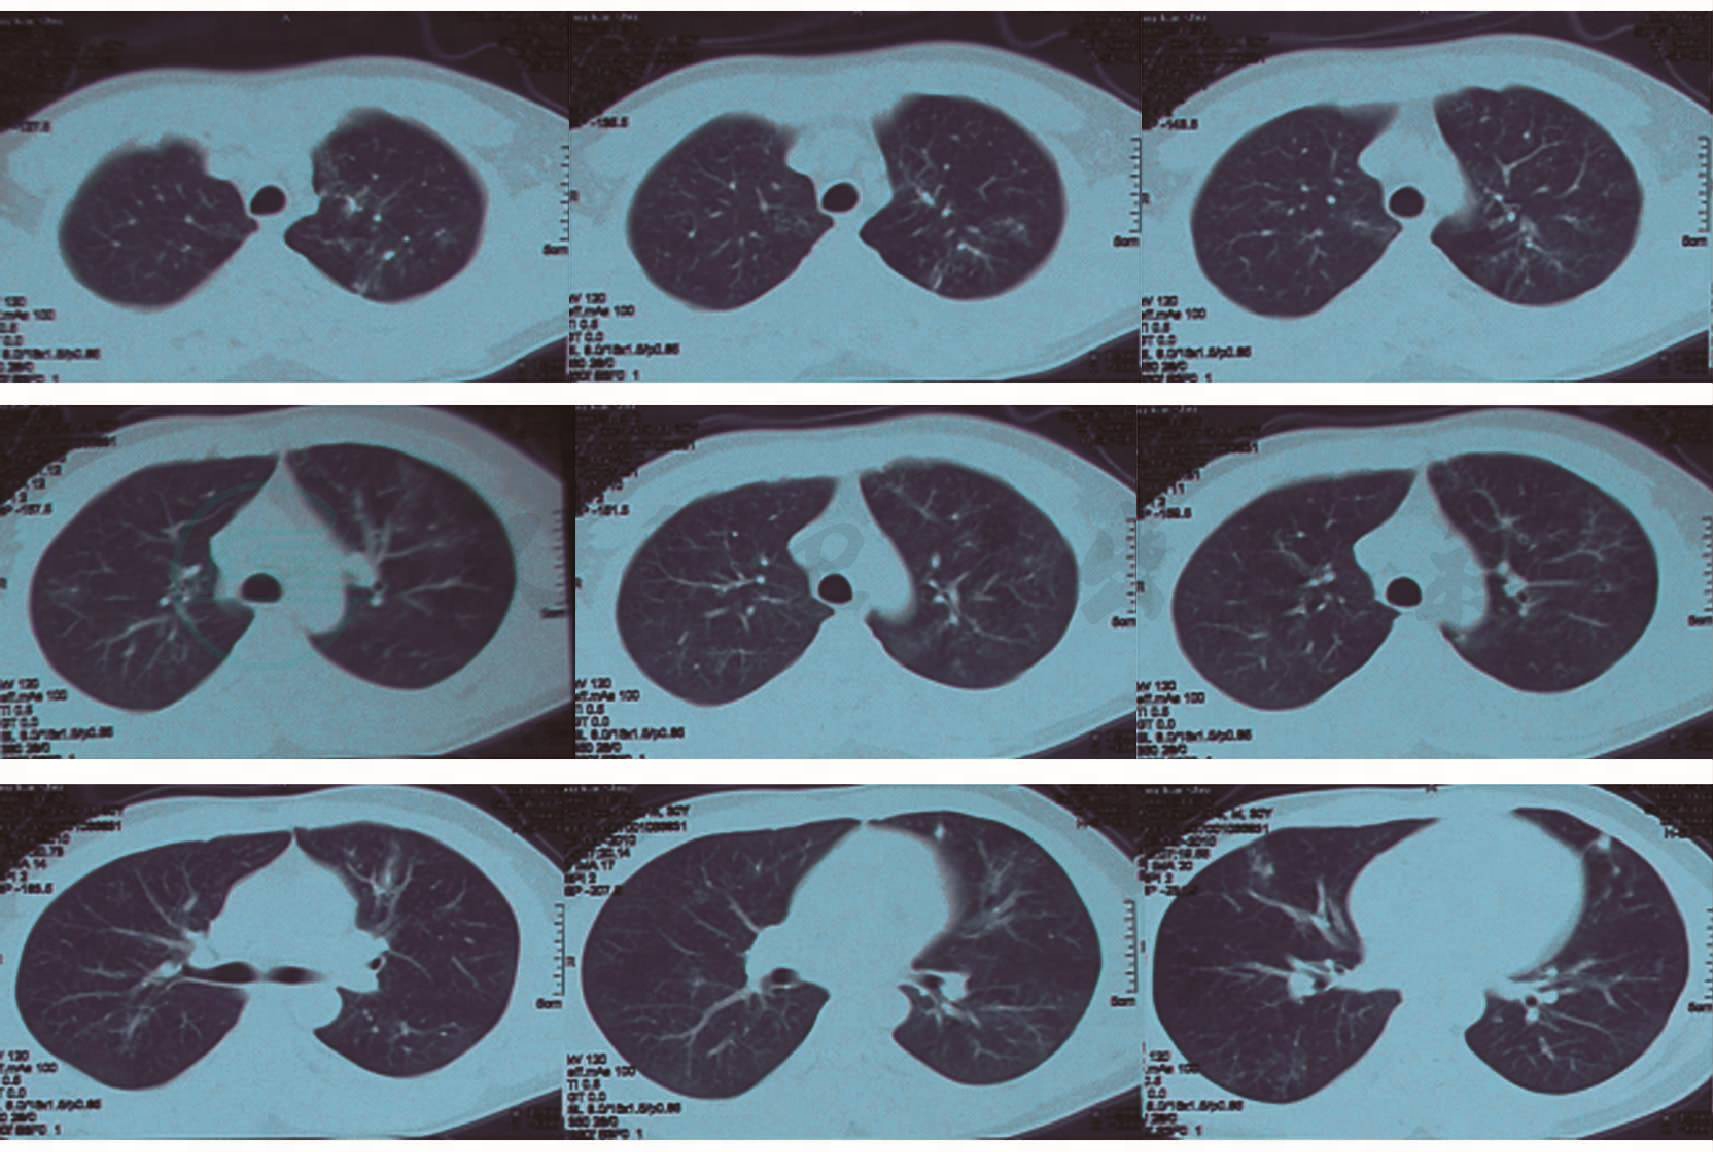

患者,男性,30岁,因咳嗽、咳痰、发热20余天,声嘶10天于2009年12月24日入院。患者于20多天前受凉后出现咳嗽、咳少量白色泡沫痰,伴畏寒、发热、活动后稍气促,最高体温39℃,以午后发热为主,无咯血、胸痛、潮热、盗汗、恶心、呕吐。自行服药(具体不详)后病情无好转,仍咳嗽、咳痰、发热。10天前无明显诱因出现声嘶,至当地医院就诊,胸部CT提示双肺见多发斑点、斑片状致密影,部分病灶内见支气管充气征(图1)。

图1 胸部CT(2009-12-10):双肺见多发斑点、斑片状致密影,部分病灶内见“支气管充气征”